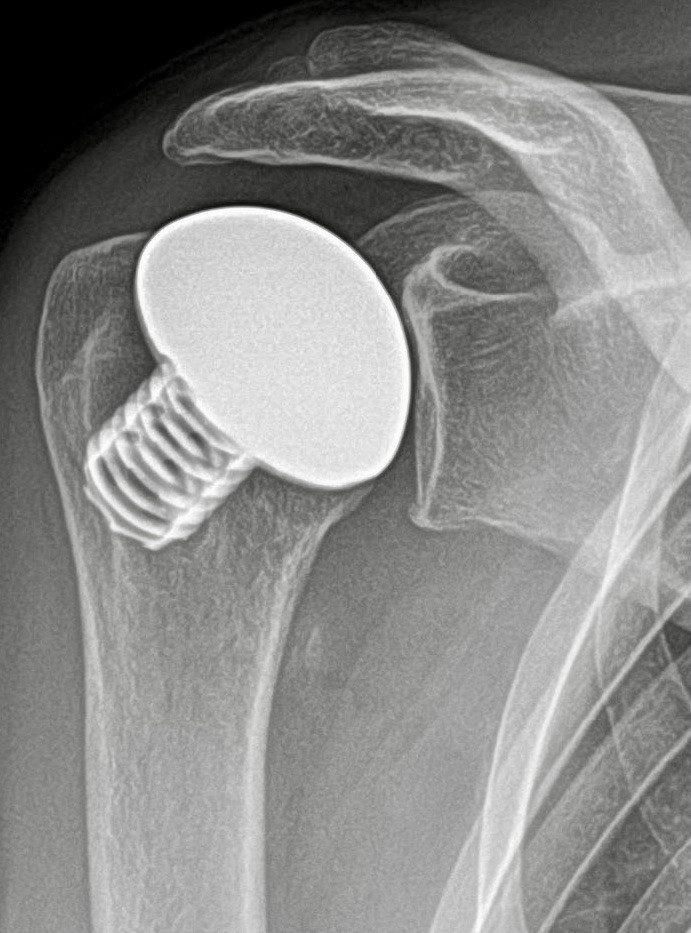

Dr. Rummel als ausgewiesener Fachmann für den Bereich der Endoprothetik erklärt „Eine fortgeschrittene Schulterarthrose, irreparable Sehnendefekte, schweres Rheuma oder ein Absterben des Oberarmkopfes können das Gelenk aber so stark schädigen, dass kein Weg an einer Prothese vorbeiführt.“ Erfreuliche Nachrichten bzgl. der Haltbarkeit hat Dr. Rummel für diese Patienten: „Nach zehn Jahren sind noch über 95% fest implantiert.“

(Bild unten: Kurzschaftprothese Schulter (Typ Eclipse, Fa. Arthrex))